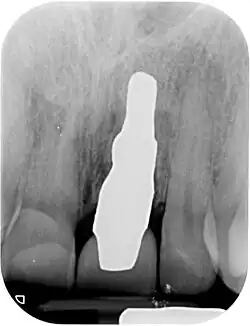

Wurzelförmige Zahnimplantate werden individuell angefertigt, damit sie unmittelbar nach der Zahnextraktion perfekt in das Zahnfach eines bestimmten Patienten passen. Jedes Implantat ist daher ein Unikat und nur für einen Patienten bestimmt. Dabei muss die ursprüngliche Wurzelform geringfügig optimiert werden, sodass es sich nicht um eine einfache 1:1-Kopie eines Zahns handelt. Das Implantat füllt genau das Knochenloch nach Extraktion aus, sodass ein chirurgischer Eingriff am Knochen oder den Weichteilen nicht erforderlich ist. Die Grundform des Implantates kann vom extrahierten Zahn, aus einem Abdruck des Zahnfaches (Alveole) oder durch Segmentation aus einem CT-Scan oder CBCT-Scan hergestellt werden.[2] Wird das Implantat aus einem CBCT-Scan hergestellt, kann die Extraktion und Implantation in einem Eingriff erfolgen. Bei den anderen beiden Methoden dauert die Herstellung eines Implantats ein bis zwei Tage.

- Einsetzen des wurzelanalogen Implantats durch Einklopfen. Im Allgemeinen ist kein chirurgischer Eingriff erforderlich. Insbesondere sind weder ein Sinuslift noch ein invasiver chirurgischer Eingriff mit Veränderung der Hart- und Weichgewebe notwendig. Das Implantat kann gleich nach der Extraktion eingesetzt werden, wenn es zuvor anhand eines CBCT-Scans erstellt wurde, oder am nächsten Tag, wenn die Wurzel gescannt werden muss oder auf Basis eines Abdruckes erstellt wird. Das Implantat wird während der frühen Einheilphase mit einer Schutzschiene oder Maryland-Brücke für 8 Wochen geschützt.

Die Patientenbelastung ist sehr kurz, da weder Weich- noch Hartgewebe durch eine Operation traumatisiert werden, die Schmerzen bereiten und anschwellen können. In der Regel treten nach dem Einsetzen des Implantats daher keine Schwellungen, Blutergüsse und mit Schmerzen ist nur für einen Tag zu rechnen. Nach einer Einheilzeit von 8–12 Wochen kann die endgültige Krone angefertigt werden.